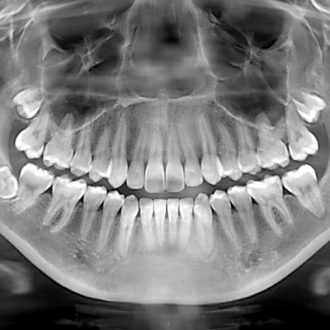

An image of the complicated state of both jaws, including the placement of all teeth, their roots, canals, and jaw